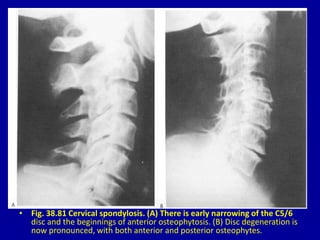

• Fig. 38.81 Cervical spondylosis. (A) There is early narrowing of the C5/6

disc and the beginnings of anterior osteophytosis. (B) Disc degeneration is

now pronounced, with both anterior and posterior osteophytes.

• Fig. 38.81Cervical spondylosis. (A) There is early narrowing of the C5/6 disc and the beginnings of anterior osteophytosis. (B) Disc degeneration is now pronounced, with both anterior and posterior osteophytes.